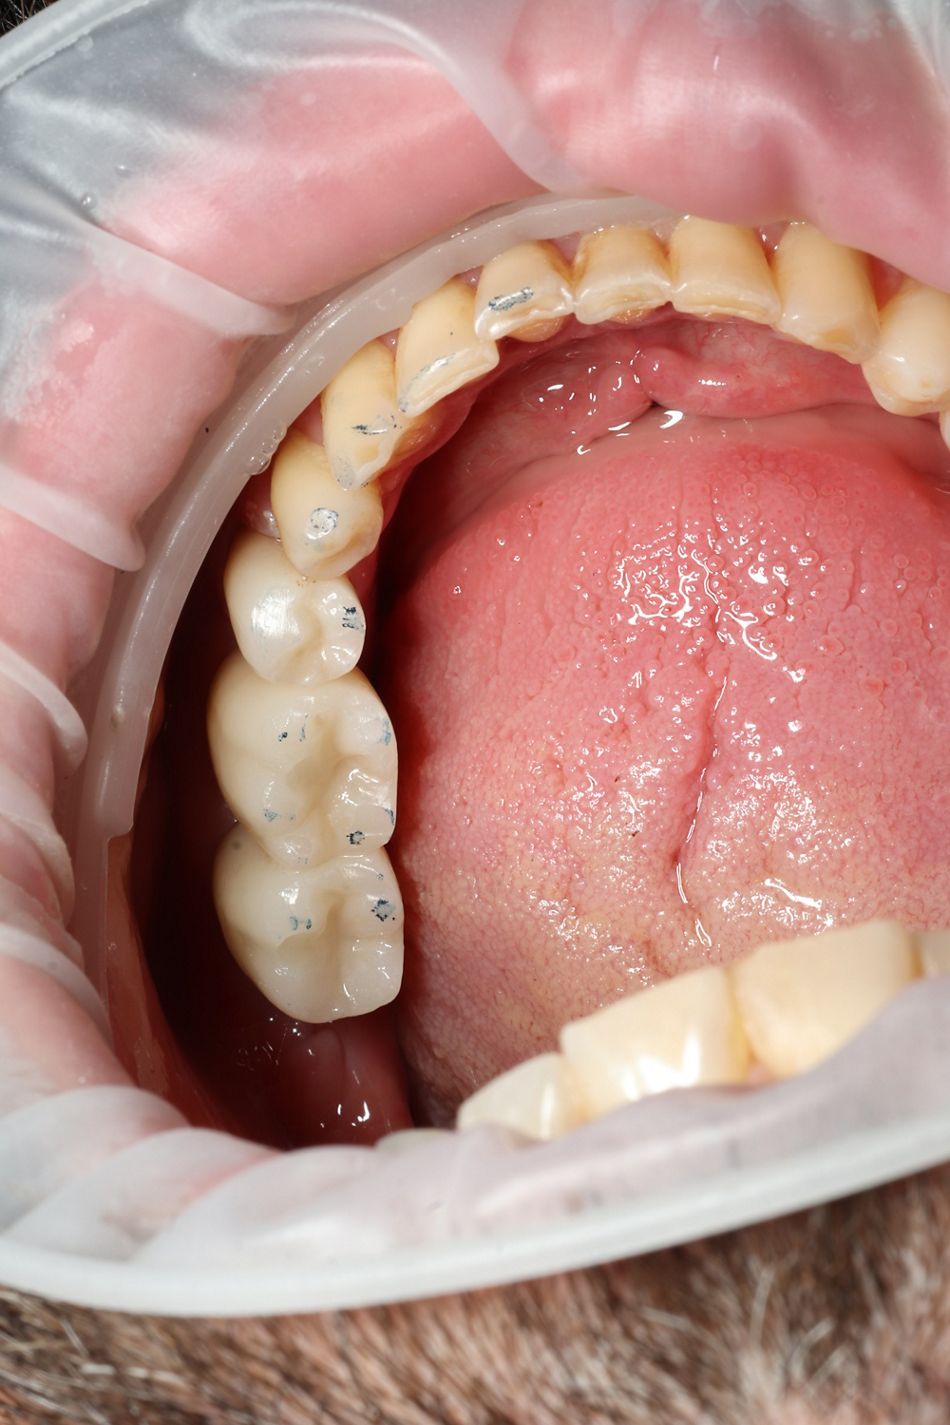

После клинических и рентгенографических оценок и рассмотрения основного запроса пациента было запланировано атравматическое удаление зубов номер 3.6 и номер 3.7 и немедленное размещение имплантатов с трансплантацией кости в нижнем жевательном отделе. Пациент согласился с этой альтернативой после подробного обсуждения различных планов лечения (Илл. 1).

Иллюстрация 1